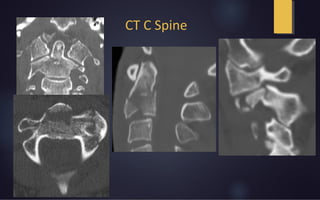

CT C Spine

Rotation on CT scan

Able to visualizing rotation and associated fractures

Dynamic CT scans are not advocated

- Risk of inducing neurological injury secondary to instability

Standard measurement technique for rotational angle